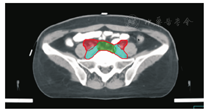

笔者所在科室对于FIGO临床分期为ⅡB期宫颈癌(阴道穹窿受侵、宫旁受侵近盆壁)的调强放疗流程及靶区CTV勾画范围建议如下。对其定位前准备工作包括:患者于定位前30~40 min排空膀胱,再饮水500 mL(含造影剂碘化醇10 mL),显影小肠。对其靶区CTV勾画具体操作步骤为:让患者取仰卧位,身下垫胸、腹平板,双手抱肘并上抬置于额头,热塑体膜固定(上腹至大腿上约1/3处);待热塑体膜冷却成形后,激光灯下于体前正中和两侧分别置铅点(尽可能靠近靶区中心)。此时尽可能行CT增强扫描,以更清楚显示解剖位置;对造影剂过敏、高龄、伴有严重并发症等不适合行CT增强扫描者,仅进行平扫。CT检查的扫描范围为:第一腰椎体上缘至坐骨结节下2 cm,层厚为5 mm,若腹主动脉旁淋巴结转移,则上移至隔顶;若全阴道浸润、腹股沟淋巴结转移,则下移至外阴下4 cm。其中,对靶区CTV勾画:放疗前,应常规实施CT、MRI或PET-CT检查,以明确肿瘤靶区范围及是否存在远处转移(部分远处转移病变,可与原发部位同时进行放疗)。对于其GTV勾画,则包括临床肉眼可见或可触及的,或可通过检查手段证实的肿瘤区域,具体包括宫颈肿瘤、受侵宫旁及阴道组织。MRI检查是确定软组织及宫旁受侵的较理想方法。若腹膜后淋巴结转移,需对淋巴结照射剂量进行加量时,CTV则应单独勾画转移淋巴结靶区。CTV勾画分为局部肿瘤区域和淋巴引流区域。局部肿瘤区域CTV勾画,包括局部肿瘤GTV及显微镜下可见的亚临床肿瘤病变,首先为宫颈、宫体、宫旁和阴道CTV勾画。①宫颈CTV:勾画全部宫颈。②宫体CTV:勾画全部宫体。③宫旁CTV:勾画上界为乙状结肠跨过子宫及输卵管处,下界为泌尿生殖膈,前界为膀胱后壁/髂外血管后缘。若子宫前倾明显,则子宫前界为宫旁前界,后界为宫骶韧带和直肠系膜前缘,内侧界为子宫颈阴道,外测界为骨盆壁,不包括肌肉和骨。值得注意的是:若宫骶韧带受累,CTV勾画则需将整个宫骶韧带全部包括在内,此时直肠系膜淋巴结及直肠周淋巴结均应包括在内。对于FIGO临床分期为ⅢB期及以上者,CTV应将直肠周淋巴结勾画在内,宫旁靶区与髂淋巴结及闭孔淋巴结区重叠。④阴道CTV:若阴道无受侵,则勾画阴道上段1/2,若上段受侵,则勾画阴道上段2/3,若阴道广泛浸润,则勾画全阴道。其次,盆腔淋巴结引流区包括宫颈旁、宫旁、闭孔、髂内、髂外、骶前及髂总淋巴结CTV勾画,依照其血管走行进行勾画。①髂总动脉CTV:上界为腹主动脉分叉下缘,下界为髂总动脉分叉下缘;前界为血管前7 mm,后界为血管后7 mm;内侧界为血管内侧7 mm,外侧界为血管外7 mm,腰大肌内侧缘,包括腰大肌与椎体旁间隙。②髂外动脉CTV:上界为髂总动脉分叉下缘,下界为股骨头上缘即股动脉;前界为血管前7 mm,后界为血管后7 mm;内侧界为血管内侧7 mm,以子宫、卵巢、肠管、输尿管及膀胱为界,外侧界为血管外7 mm,腰大肌及髂腰肌内侧缘。③髂内动脉CTV:紧邻髂内血管及其分支,上界为髂总动脉分叉下缘,下界为尾骨肌上缘、坐骨棘或子宫动静脉上端;前界为血管外7 mm,后界为上部以骶骨翼为准,中下部至梨状肌前缘或臀下动静脉;内侧界为血管外7 mm,外侧界为头侧髂腰肌、髂肌或骶髂关节外侧,中间为髂骨、髂腰肌或髂肌内侧缘;尾侧界为闭孔内肌或梨状肌内侧。④闭孔淋巴结CTV:上界为骶髂关节下缘连接至髂内淋巴结,下界为闭孔上缘;前界为上中部分连接到髂外,下部至耻骨后缘,后界上中部连接到髂内,下部至闭孔内肌后缘;内侧界至膀胱、子宫及肠管,沿骨盆壁向内扩18 mm,外侧界至闭孔内肌、髂肌、髂腰肌或髂骨。⑤骶前淋巴结CTV:上界为髂总分勾画范围,见图1,图2,图3,图4,图5,图6。